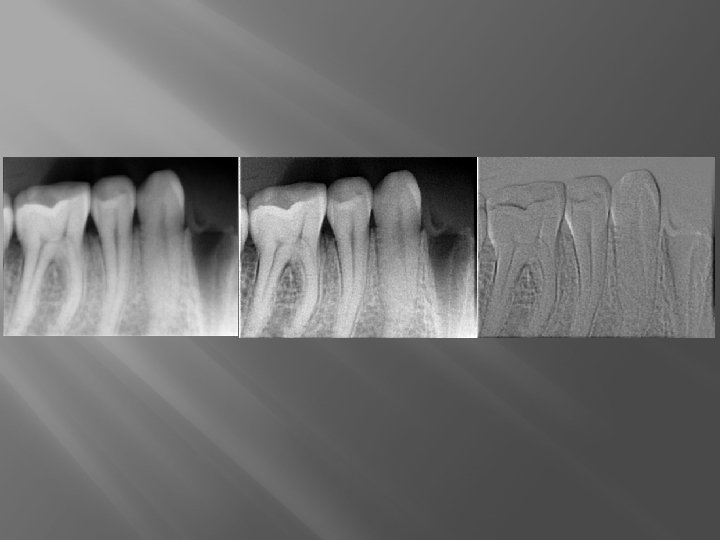

A digitális radiográfia sugárvédelmi vonatkozásai � � � Az intraoralis felvételeknél kisebb a sugárdózis Elektronikusan archiválható, sokszorozható (az ismétlések kikerülhetőek) A software előnye: � Megspórolhatunk újabb felvételeket A túl-, vagy alulexponált filmek megmenthetők Nagyítani tudunk Változtathatjuk a kontrasztot, az élességet